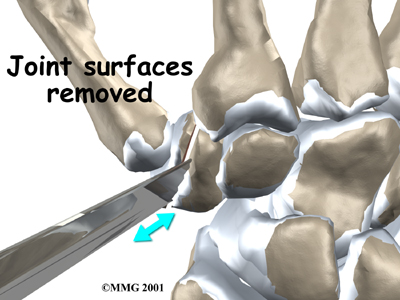

In this procedure, an incision is made across the base of the thumb. The soft tissues are spread apart with a retractor. Special care is taken not to damage the nearby nerves going to the thumb. The joint capsule is opened, exposing the CMC joint. The ends of the bones that form the CMC joint surfaces are taken off, forming flat surfaces.

A new method for replacing the thumb joint is to use a spherical implant that looks much like a marble. The surgeon makes a small, one-inch incision at the base of the thumb joint. The ends of the bones that form the CMC joint surfaces are removed, forming flat surfaces.

View animation of joint surface removal